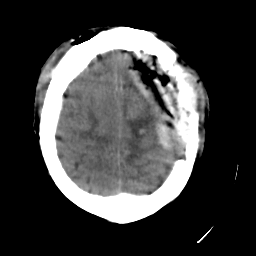

Meningioma: Roentgen-ray CT #1 -- Slice #18

[Home][Help][Clinical] Slice 18